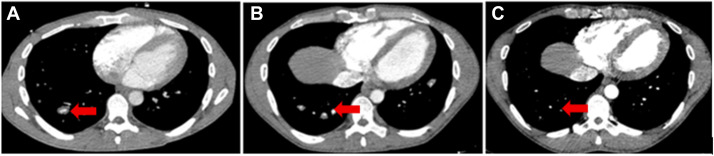

胸部增强CT:可见新发、多发的肺动静脉扩张伴动脉瘤样改变,且存在原位血栓形成,伴肺动脉分支周围散在软组织增厚(2023.11.03)。

图 1 A:治疗前可见肺动脉分支周围散在血管旁软组织增厚,伴多发微小动脉瘤形成,高度提示血管炎改变。 B:使用

治疗后数周内,患者体温快速恢复正常,炎症标志物降至正常,咯血症状完全缓解;治疗6个月后胸部CT复查,肺动脉瘤的大小及数量均较前改善,仅下叶仍见小动脉瘤,血管周围炎症较前缓解(2024.09.29)。

英夫利昔单抗治疗6个月后胸部CT复查:肺动脉血管周围增厚及动脉瘤样改变完全消退(2025.04.28);后续予英夫利昔单抗维持剂量输注联合全剂量抗凝治疗9个月,患者未再出现症状复发及新的咯血事件。